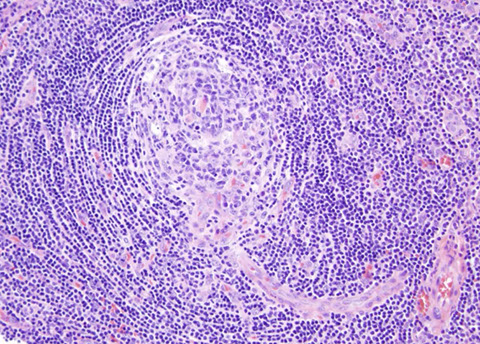

Toxoplasma lymphadenitis. Has lots of reactive follicles, intact capsule with patent subcapsular sinus getting closer to hilum. Increased follicles almost back to back, but have well-preserved and well-defined mantle zones and preservation of the interfollicular areas. There are lots of pinkish cells, which are epithelioid histiocytes which surround and encroach upon involved follicles [3]

Epithelioid histiocytes in toxoplasma infection [3]

Monocytoid B-cells in Toxoplasma lymphadenitis [7]

Classic triad of monocytoid cells, enlarged follicles with reactive germinal centers, and epithelioid histiocytes encroaching germinal centers in Toxoplasma [7]